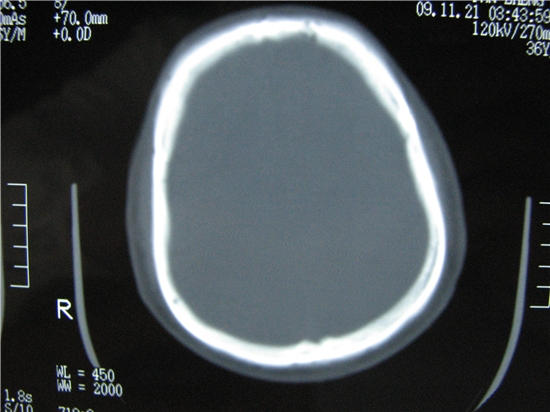

额窦里是什么,骨窗怎么不清晰,是不窗宽窗位的事。

额窦内及额部软组织内可见多发游离类骨质密度影,考虑额骨骨折可能。

额窦致密骨瘤,前额部及右顶部头皮损伤伴异物存留

左侧额骨、鼻骨骨折,头面部软组织肿胀。

左侧额骨、鼻骨骨折,额窦内的应该是游离骨块